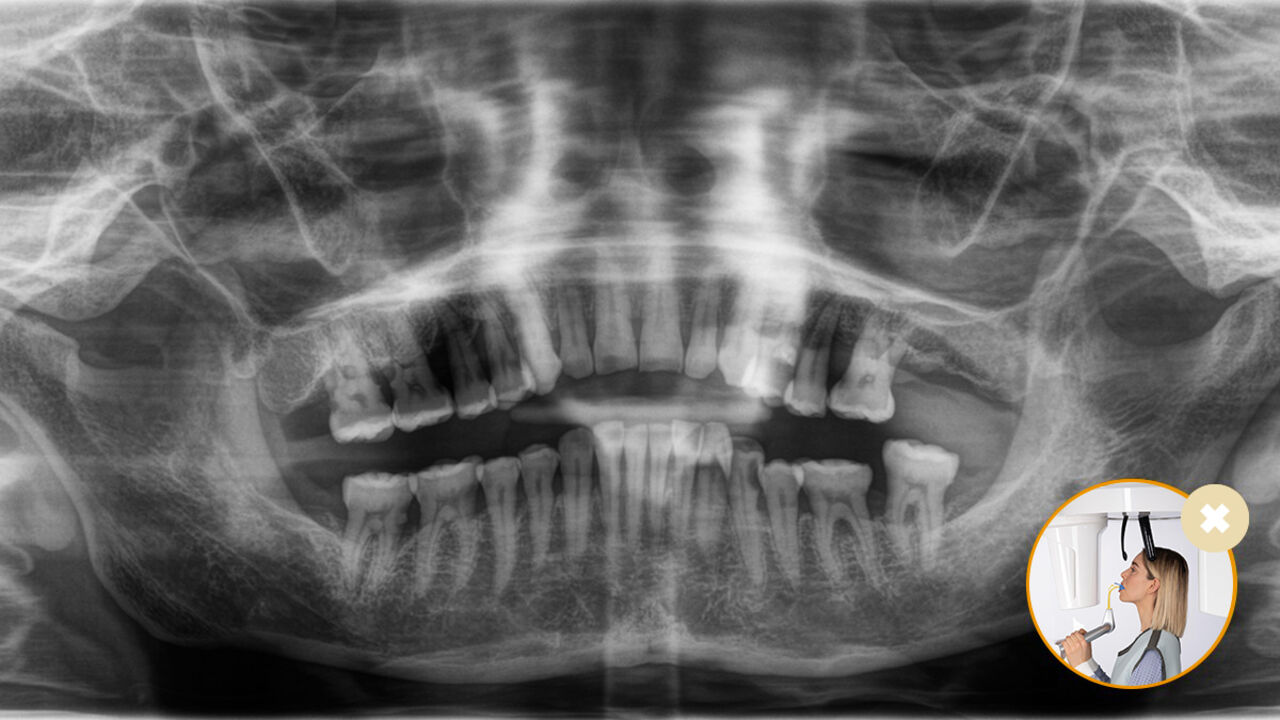

Correct patient positioning leads to high image quality to support an accurate diagnosis and facilitates and improves patient experience.

This is our 10-point concept for easy patient positioning and X-ray imaging. It is primarily about two things: high image quality and comfort for the patient and the assistant.